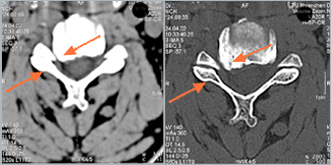

Computertomographie (CT): Halswirbelsäule mit rechts- betonter beidseitiger Foramenstenose